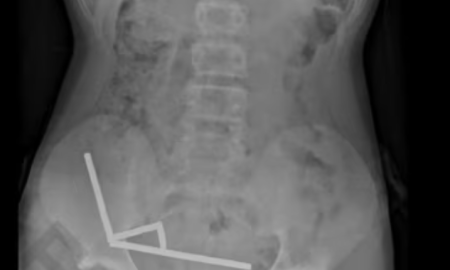

Trinaestogodišnjem dječaku na Novom Zelandu odstranjen je dio crijeva nakon što je progutao gotovo 200 snažnih magneta. Dječak se brzo oporavio nakon...